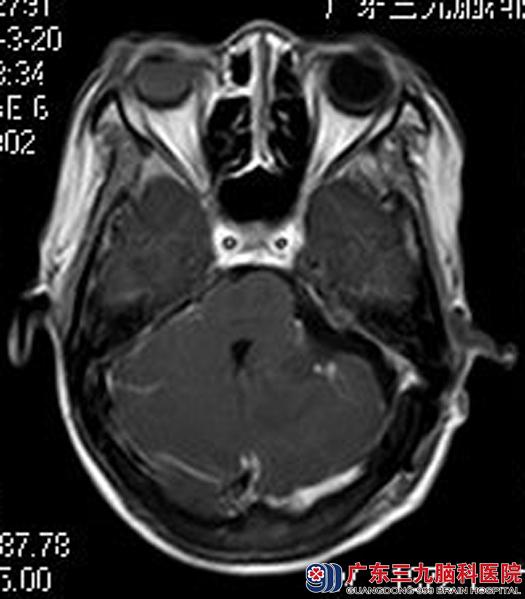

综合神经外科鲁明主任主刀,在全麻下行左侧桥小脑角肿瘤切除术,术中见左侧小脑外侧前缘有一稍透明样肿瘤生长,边界稍清楚,质地中,血供较丰富。置显微镜,沿肿瘤靠近颅骨处切除肿瘤根部,肿瘤根部靠近蝶骨脊后缘骨膜上,左侧面神经及听神经被挤压至小脑表面,肿瘤血肿一般,分块切除肿瘤。电生理监测保护下切除肿瘤,神经保留完整,手术顺利,术后无后组颅神经损害症状,偏头痛也没再光临。术后病理结果:纤维型脑膜瘤。

▲手术后